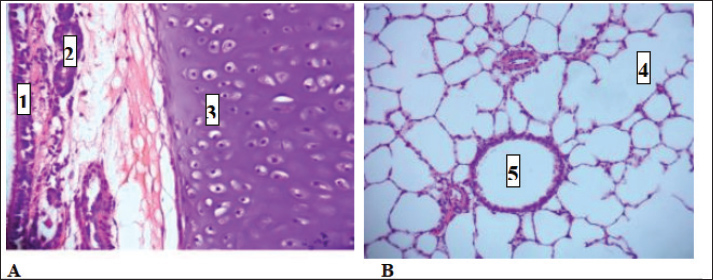

Fig. 5. Control group (A) trachea (1)mucosal layer has ciliated pseudostratified epithelia (2)tracheal gland (3) Hyaline cartilage and (B) lung show (4)Alveolar sac (5) terminal bronchioles and had no pathological change of organ H&E stain 400X 200X respectively

Fig. 6. Group of infected rabbits lung (A) Bronchiols show emphysema aggregation of lymphocytic cell (black arrow)( B) show emphysema structure atelectasis (black arrow) H&E stain 400X and lung H&E stain 200X. Gross examination of sacrificed animals (group of infected rabbits) showed hemorrhage in the upper respiratory tract (Fig. 3). The trachea exhibited a semi-circular hyaline cartilage structure (Fig. 4), and the bronchi branched into left and right bronchioles, consistent with typical mammalian respiratory anatomy. Normal histological details of trachea of control group• Tunica mucosa • Tunica submucosa • Tunica adventitia • C-shaped hyaline cartilage (Fig. 5A) • score lesion of Pathological Changes • Emphysema was observed in 3 out of 5 cases (60%) (Fig. 4). • No pathological changes were seen in 2 cases (40%). • Vascular changes, including congestion, thrombosis, and alveolar hemorrhage, were noted in 10% of affected cases. Comparative morphologyLight microscopy analysis confirmed Gram-negative rods for Raoultella planticola. However, differentiation from Klebsiella spp. was challenging due to morphological similarities (Fig. 2A and B). The histological findings of emphysema and atelectasis align with Blagojević et al. (2018), who described similar structural changes in respiratory infections. The observed hemorrhage and vascular congestion support Castro et al. (2001), who linked these changes to bacterial-induced trauma. The 60% incidence of emphysema suggests that Raoultella planticola primarily induces chronic obstructive pulmonary disease (COPD)-like lesions, differing from Sarhad (2011), who reported fibrinous pleuropneumonia as the dominant pathology. This discrepancy may stem from differences in infection routes or host susceptibility. The short respiratory passage and direct bronchial branching in rabbits (Abdelsalam and Al Sadrani, 2015) likely contribute to higher lung infection rates. Additionally, the similarity between Raoultella and Klebsiella (Alampoondi Venkataramanan et al., 2021) complicates microscopic differentiation, necessitating advanced diagnostic methods like Vitek2.Contrary to Vinshia, J. J., (2024), this study found no fibrinous bronchopneumonia, instead emphasizing edema and congestion (Das and Bhagman, 1997). The reclassification of Raoultella from Klebsiella prior to 2001 further underscores the need for precise microbiological identification (Fig. 8). This study highlights Raoultella planticola's potential to cause respiratory pathology, warranting further investigation into its zoonotic risks.